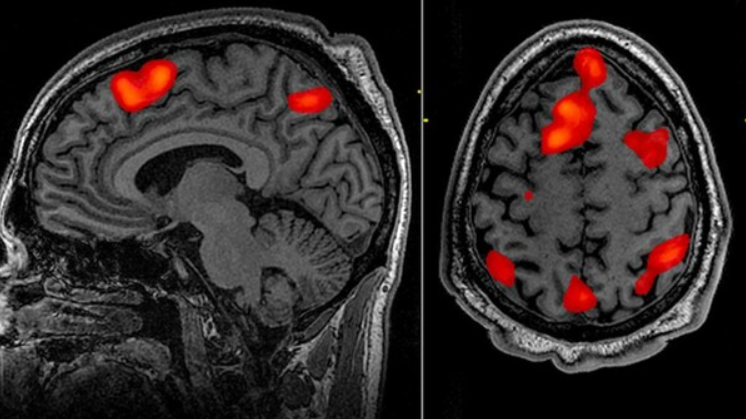

인지 신경과학은 간단히 말해 "우리의 뇌(신경)가 어떻게 생각(인지)을 만들어내는가"를 연구하는 학문이다. 과거에는 심리학이 마음의 작용을 관찰하고, 생물학이 뇌의 구조를 연구하며 각자의 길을 걸었다. 하지만 20세기 후반 fMRI(자기 공명영상) 같은 기술이 발전하면서, 사람이 특정 생각을 할 때 뇌의 어느 부위가 활성화되는지 실시간으로 관찰할 수 있게 되었고, 심리학과 뇌 영상 기술이 결합하며 인지 신경과학이라는 독자적인 영역이 탄생했다.

- fMRI (기능적 자기공명영상): 특정 과제를 수행할 때 혈류량이 증가하는 뇌 부위를 촬영한다. '어디서' 인지 작용이 일어나는지 아는 데 탁월하다.